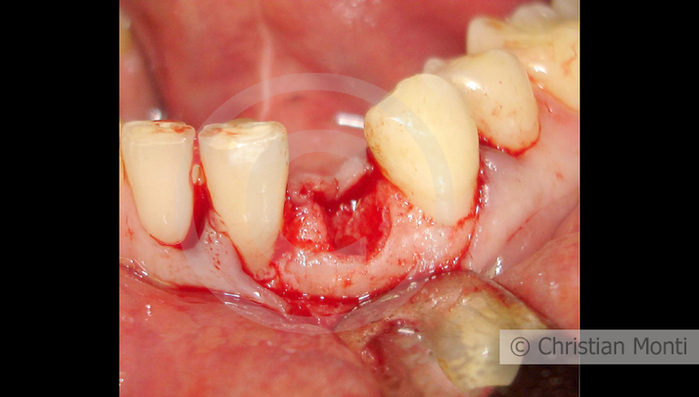

EDENTULIA SINGOLA

Impianto in sostituzione di un canino deciduo